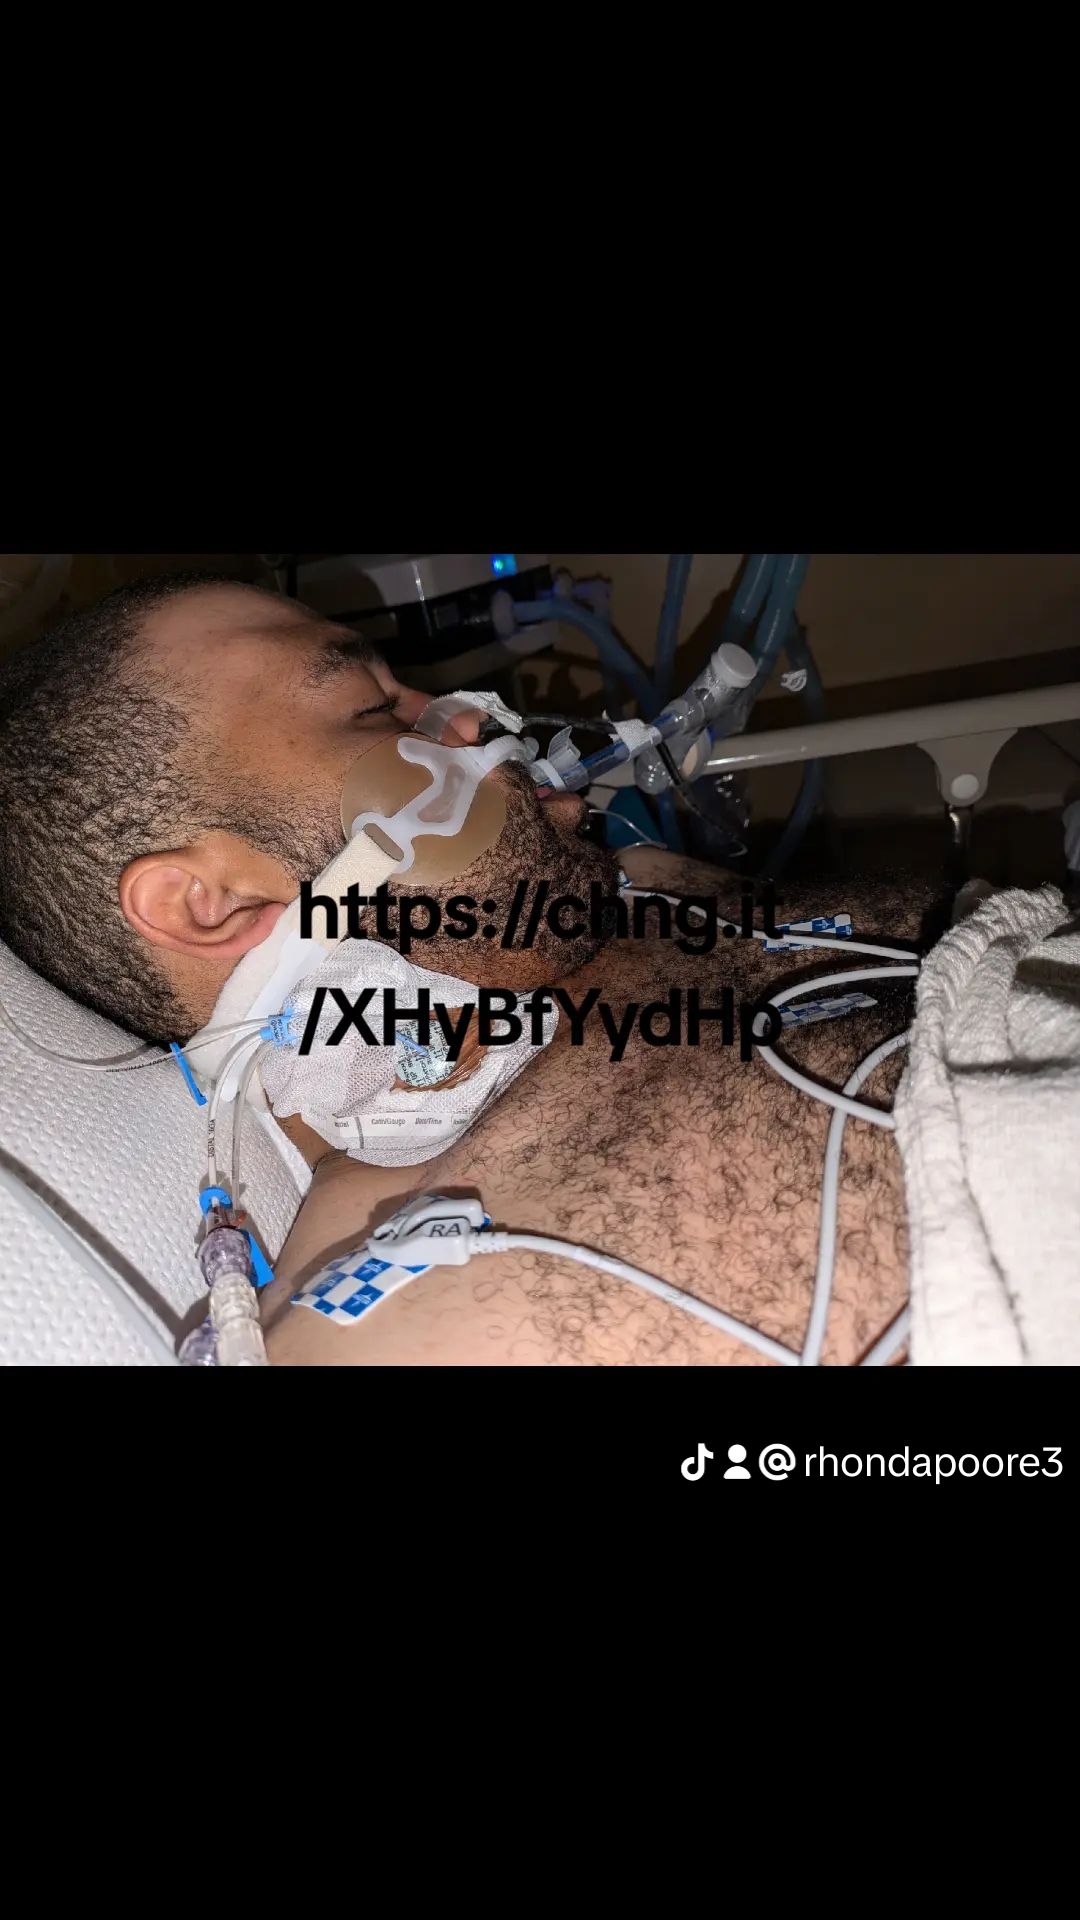

I am a mother, standing helplessly by my son's bedside as he lays on life support. The culprit? A readily available over-the-counter cold and cough medicine like Coricidin which he overdosed on. I am starting this petition because I believe it is a pressing issue that needs to be addressed immediately. Far too many products that have lethal potential when abused are freely accessible on store shelves.

My son is on life support and may not survive. This painful situation raises the question: why are we placing sinus medications behind the counter while leaving something more lethal out in the open? It's time to enact stricter regulations on the sale of these medications, to minimize the risk of misuse and save lives.

We are calling for explicit regulations that require medicines like Coricidin be placed behind the counter, out of easy reach, and sold only under certain conditions to people of appropriate age. Let's prevent another family from experiencing the horror and heartbreak of seeing a loved one on life support due to easily accessible over-the-counter medication. Please, sign this petition and help prevent more tragedies. .mentalwellness#suicidepreventionOk I want to have a discussion people may not understand. My son did not overdose from getting high . He is mentally ill and tried to commit suicide. I have had many of my friends (supposedly) look at my petition not sign and not even say a word to me at all so let me explain to people why this is important. Kids , teenagers and addicts use this to get high . They call it skittles, or triple C's since 2009 many people in the whole world have died . It is considered an opiate . Why should an opiate not be regulated. Im not trying to ban this drug but its very dangerous it causes heart damage can cause brain damage if you take more than 4 in a 24 hour period . Its an opioid that at least needs to be behind the counter and people dont need to be able to buy boxes and boxes at one time. Im trying to do this for the future families that may end up In my situation whether its an addiction issue a teenager trying to get high because they can legally go buy that high for cheap or mentally ill people.Im not doing this for Eric because I realize he can attempt suicide with other things and other ways. Im trying to save other families. Dxm youngest victim was a 12 year old something so dangerous that children use to get high and classified an opiate should not be unregulated. Im on here and share everyone's causes business campaign runs etc. With my cause 617 people have viewed my petition and 58 have signed . Times like this show you who your friends truly are

I am a mother, standing helplessly by my son's bedside as he lays on life support. The culprit? A readily available over-the-counter cold and cough medicine like Coricidin which he overdosed on. I am starting this petition because I believe it is a pressing issue that needs to be addressed immediately. Far too many products that have lethal potential when abused are freely accessible on store shelves.

My son is on life support and may not survive. This painful situation raises the question: why are we placing sinus medications behind the counter while leaving something more lethal out in the open? It's time to enact stricter regulations on the sale of these medications, to minimize the risk of misuse and save lives.

We are calling for explicit regulations that require medicines like Coricidin be placed behind the counter, out of easy reach, and sold only under certain conditions to people of appropriate age. Let's prevent another family from experiencing the horror and heartbreak of seeing a loved one on life support due to easily accessible over-the-counter medication. Please, sign this petition and help prevent more tragedies. .mentalwellness#suicidepreventionOk I want to have a discussion people may not understand. My son did not overdose from getting high . He is mentally ill and tried to commit suicide. I have had many of my friends (supposedly) look at my petition not sign and not even say a word to me at all so let me explain to people why this is important. Kids , teenagers and addicts use this to get high . They call it skittles, or triple C's since 2009 many people in the whole world have died . It is considered an opiate . Why should an opiate not be regulated. Im not trying to ban this drug but its very dangerous it causes heart damage can cause brain damage if you take more than 4 in a 24 hour period . Its an opioid that at least needs to be behind the counter and people dont need to be able to buy boxes and boxes at one time. Im trying to do this for the future families that may end up In my situation whether its an addiction issue a teenager trying to get high because they can legally go buy that high for cheap or mentally ill people.Im not doing this for Eric because I realize he can attempt suicide with other things and other ways. Im trying to save other families. Dxm youngest victim was a 12 year old something so dangerous that children use to get high and classified an opiate should not be unregulated. Im on here and share everyone's causes business campaign runs etc. With my cause 617 people have viewed my petition and 58 have signed . Times like this show you who your friends truly are